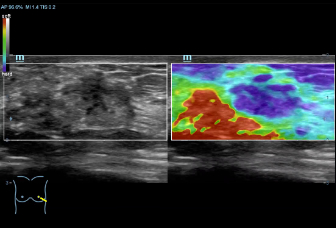

DC-70 Exp

–Ш–љ—Б—В—А—Г–Љ–µ–љ—В –і–ї—П –≤—Л—Б–Њ–Ї–Њ–Ї–∞—З–µ—Б—В–≤–µ–љ–љ–Њ–є –і–Є–∞–≥–љ–Њ—Б—В–Є–Ї–Є

X-Insight вАУ —Н—В–Њ –Њ—В–ї–Є—З–љ–Њ–µ —А–µ—И–µ–љ–Є–µ –і–ї—П –Њ–њ—А–µ–і–µ–ї–µ–љ–Є—П –љ–Њ–≤—Л—Е –≤–Њ–Ј–Љ–Њ–ґ–љ–Њ—Б—В–µ–є.

–°–Њ–≤–Љ–µ—Б—В–љ–Њ —Б —Б–Њ–≤—А–µ–Љ–µ–љ–љ—Л–Љ–Є —Г–ї—М—В—А–∞–Ј–≤—Г–Ї–Њ–≤—Л–Љ–Є —В–µ—Е–љ–Њ–ї–Њ–≥–Є—П–Љ–Є –љ–Њ–≤–Њ–µ —А–µ—И–µ–љ–Є–µ –Њ—В Mindray –њ—А–µ–Њ–±—А–∞–Ј—Г–µ—В –∞–Ї—В—Г–∞–ї—М–љ—Л–µ –Ј–∞–і–∞—З–Є –Ї–ї–Є–µ–љ—В–Њ–≤ –≤ –Ї–ї–Є–љ–Є—З–µ—Б–Ї–Є–µ –њ–Њ—В—А–µ–±–љ–Њ—Б—В–Є.

–°–Є—Б—В–µ–Љ–∞ DC-70 Exp —Б X-Insight –њ–Њ–Љ–Њ–≥–∞–µ—В —Г–њ—А–∞–≤–ї—П—В—М –њ–Њ–≤—Б–µ–і–љ–µ–≤–љ–Њ–є –Ї–ї–Є–љ–Є—З–µ—Б–Ї–Њ–є –њ—А–∞–Ї—В–Є–Ї–Њ–є —Б –ї–µ–≥–Ї–Њ—Б—В—М—О –Є —Г–≤–µ—А–µ–љ–љ–Њ—Б—В—М—О.

–Ю—Б–љ–Њ–≤—Л–≤–∞—П—Б—М –љ–∞ –≥–ї—Г–±–Њ–Ї–Њ–Љ –њ–Њ–љ–Є–Љ–∞–љ–Є–Є –њ–Њ—В—А–µ–±–љ–Њ—Б—В–µ–є –Ї–ї–Є–µ–љ—В–Њ–≤, –Ї–Њ–Љ–њ–∞–љ–Є—П Mindray —А–∞–Ј—А–∞–±–Њ—В–∞–ї–∞ —Б–Є—Б—В–µ–Љ—Г DC-70 Exp —Б X-Insight, —З—В–Њ–±—Л –Њ–±–µ—Б–њ–µ—З–Є—В—М eXpress Clarity, eXceptional Intelligence, eXceeding Experience.